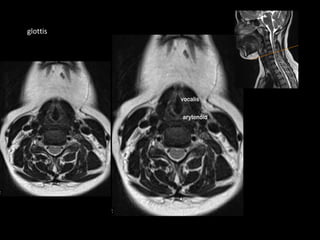

supraglottis

glottis